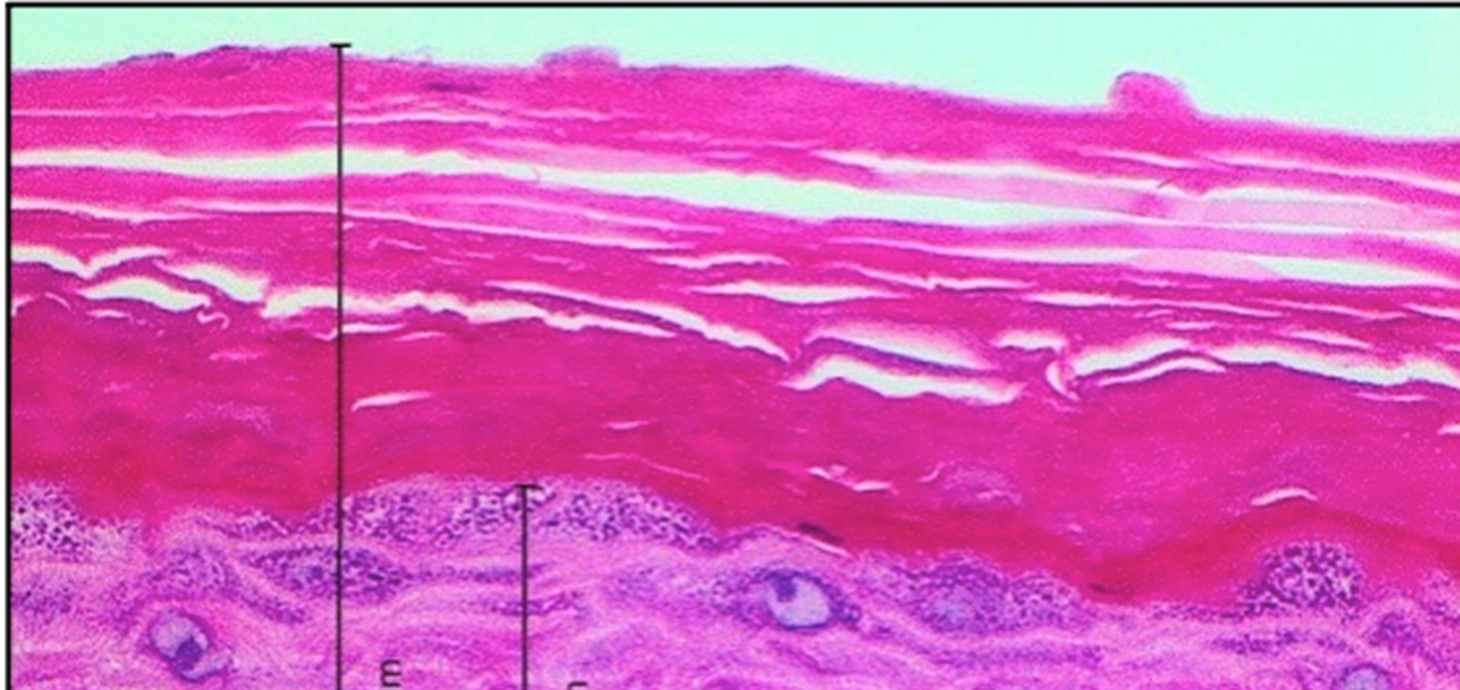

Croen: mae’r prosiect CALIN yn archwilio’r rhyngweithiad rhwng systemau byw neu feinweoedd a deunyddiau megis nanoronynnau neu ddeunyddiau nanostrwythuredig,

Mae'r Rhwydwaith Arloesi Celtaidd ar gyfer Gwyddorau Bywyd Uwch (CALIN), sy'n cynnwys tair prifysgol yng Nghymru a thair prifysgol yn Iwerddon, dan arweiniad Prifysgol Abertawe, yn tanlinellu pwysigrwydd ymchwil i fyd diwydiant lleol. Mae'r prosiect hwn yn cynnig cyfleoedd ymchwil a datblygu i fusnesau bach a chanolig yn y sector, gan ddarparu mynediad agored at arbenigwyr a chyfleusterau o ran y gwyddorau bywyd. Fe'i hariannwyd yn rhannol gan Gronfa Datblygu Rhanbarthol Ewrop a rhaglen cronfeydd Iwerddon-Cymru yr UE.

Mae gwyddonwyr CALIN wedi gweithio gyda Virustatic, sy'n datblygu atebion sy'n seiliedig ar brotein ar gyfer amrywiaeth o ddiwydiannau, gan gynnwys meddyginiaethau, iechyd menywod a thecstilau gwrthficrobaidd, gan leihau'r ddibyniaeth ar gyfansoddion cemegol sy’n niweidiol ac sy'n achosi llygredd. Cynnyrch mwyaf adnabyddus CALIN yw Virustatic SHIELD®, technoleg hidlo feirysau arloesol, a enillodd Wobr Arloesi MediWales.